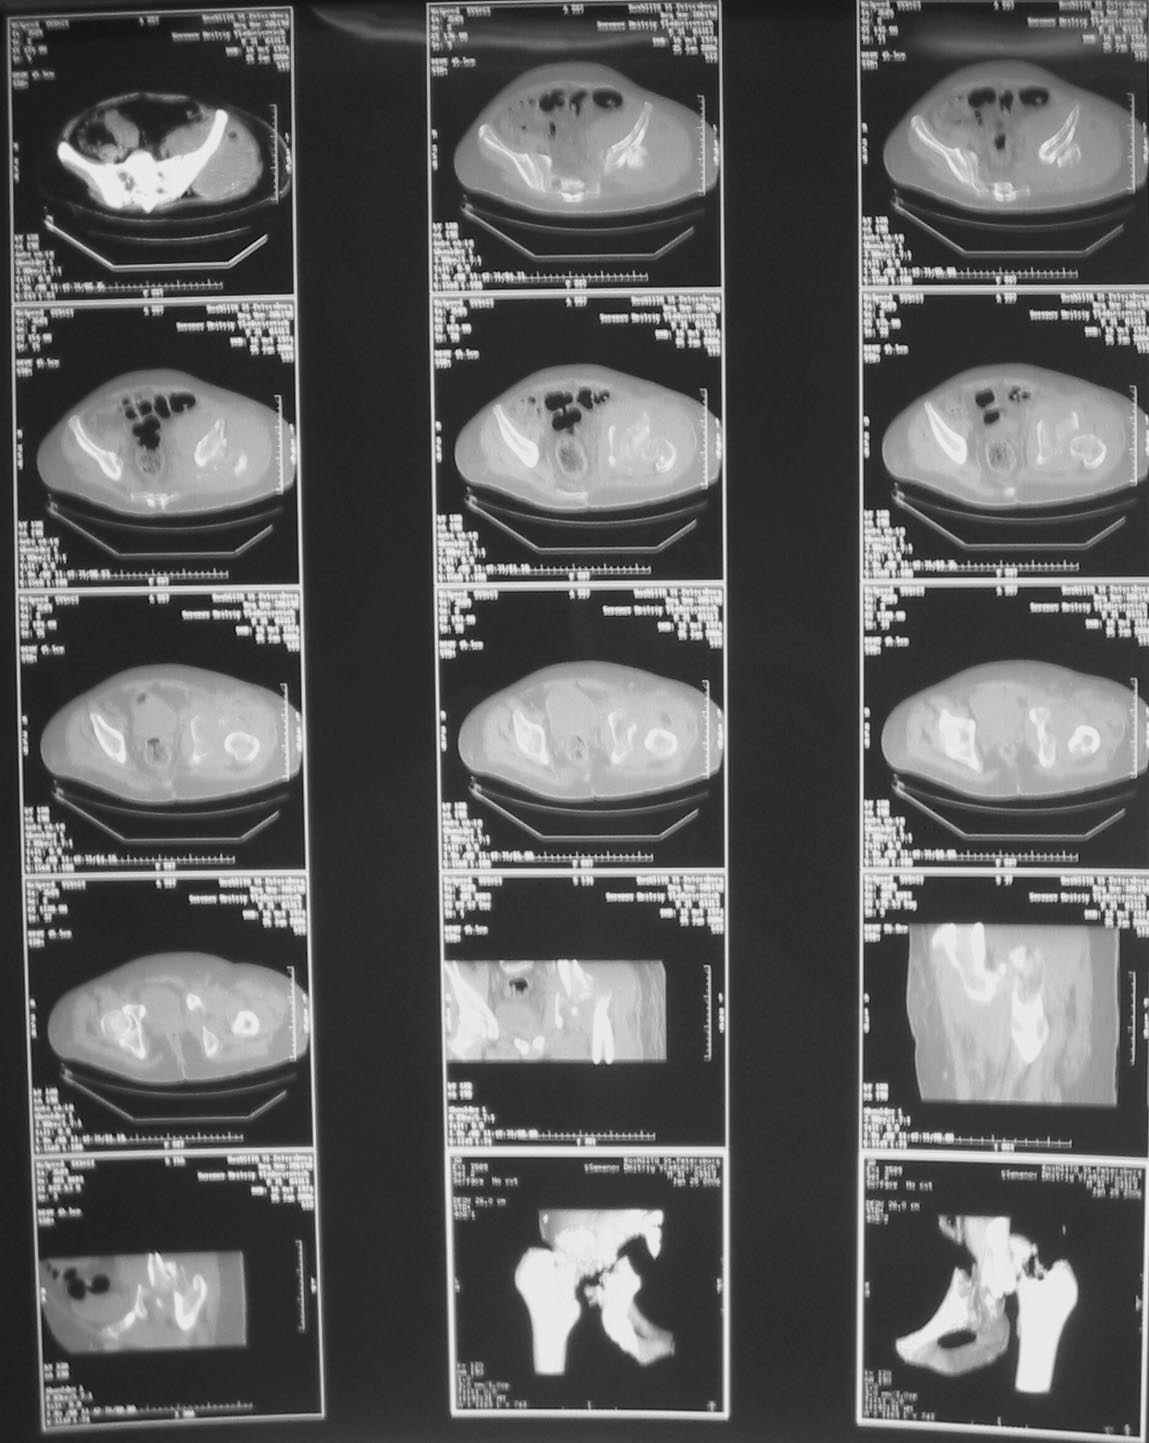

Таз+шейка

Дорогие коллеги, Поступил пациент, 5 месяцев, как сломался.

Поступил для эндопротезирования, но наши корифеи засомневались, не собрать ли сначала таз. Есть ли смысл собирать аппаратом закрыто?

Вариант с постепенной репозицией возможен, у нас такие операции были - аппаратом с введением стержней через вертельную зону в лонно-седалищный фрагмент с подтягиванием его латерально и дистально до максимального контакта задней колонны, затем открытый остеосинтез впадины с заполнением дефекта всем, чем попало. Через 2-3 мес. - эндопротез стандартным доступом, делали винтовую чашку.

Однако, учитывая вывих, 5-месячный срок мы бы, наверно, без аппарата сразу забрались в сустав с целью его реконструкции и остеосинтеза винтами и пластинами. Если удастся сделать остеосинтез хорошо - сразу сделать и эндопротез. Доступ - есссно, не как на протез, а как на впадину - или Y-образный с остеотомией болшого вертела, или латеральный. В случае подозрения на нестабильность впадины после остеосинтеза или больших трудностей при синтезе - засунуть головку во впадину, сделать остеосинтез шейки винтами, и дождаться сращения впадины, попытавшись сохранить движения в суставе. Пишут, можно противопротрузионными кольцами или Octopus укрепить остеосинтез впадины, и тогда тоже делать протез сразу, но у нас такого опыта нет, в основном предпочитали делать в два этапа - сначала реконструкция впадины, потом протез, потому что в застарелых случаях впадина сильно кривая.